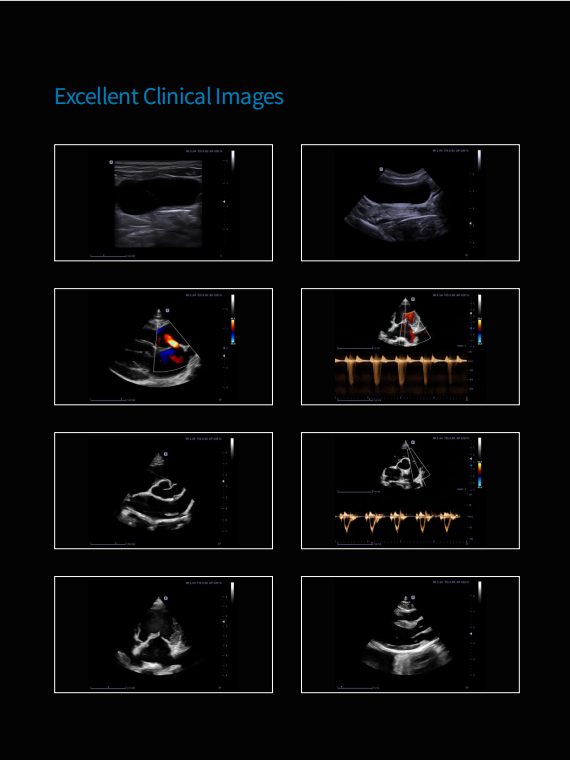

Excellent Image Performance

·Tissue Doppler Imaging ·Compounding Imaging ·Speckle Noise Suppression ·Tissue Harmonic Imaging